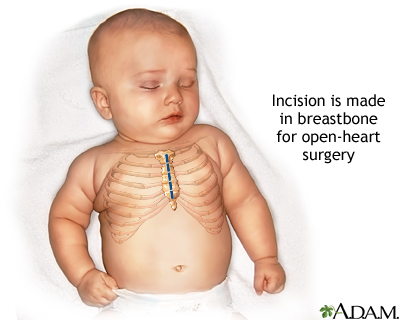

Congenital heart defect corrective surgery fixes or treats a heart defect that a child is born with. A baby born with one or more heart defects has congenital heart disease. Surgery is needed if the defect could harm the child's long-term health or well-being. Sometimes, congenital heart disease is not detected until adulthood.

There are many types of pediatric heart surgery.

- Open-heart surgery may also be done to repair ASD. In this operation, the septum can be closed using stitches. Another way to cover the hole is with a patch.

- Larger VSDs and small ones in certain parts of the ventricular septum, or ones that cause heart failure or endocarditis, (infection) need open-heart surgery. The hole in the septum is most often closed with a patch.

- Open-heart surgery is needed, and it is often done when the child is 6 months to 2 years old.

- Correcting transposition of the great vessels requires open-heart surgery. If possible, this surgery is done shortly after birth.

- Truncus arteriosus is a rare condition that occurs when the aorta, coronary arteries, and pulmonary artery all come out of one common trunk from the heart. The disorder may be very simple, or very complex. In all cases, it requires open-heart surgery to repair the defect.

- TAPVR repair requires open-heart surgery. The pulmonary veins are routed back to the left side of the heart, where they belong, and any abnormal connections are closed.